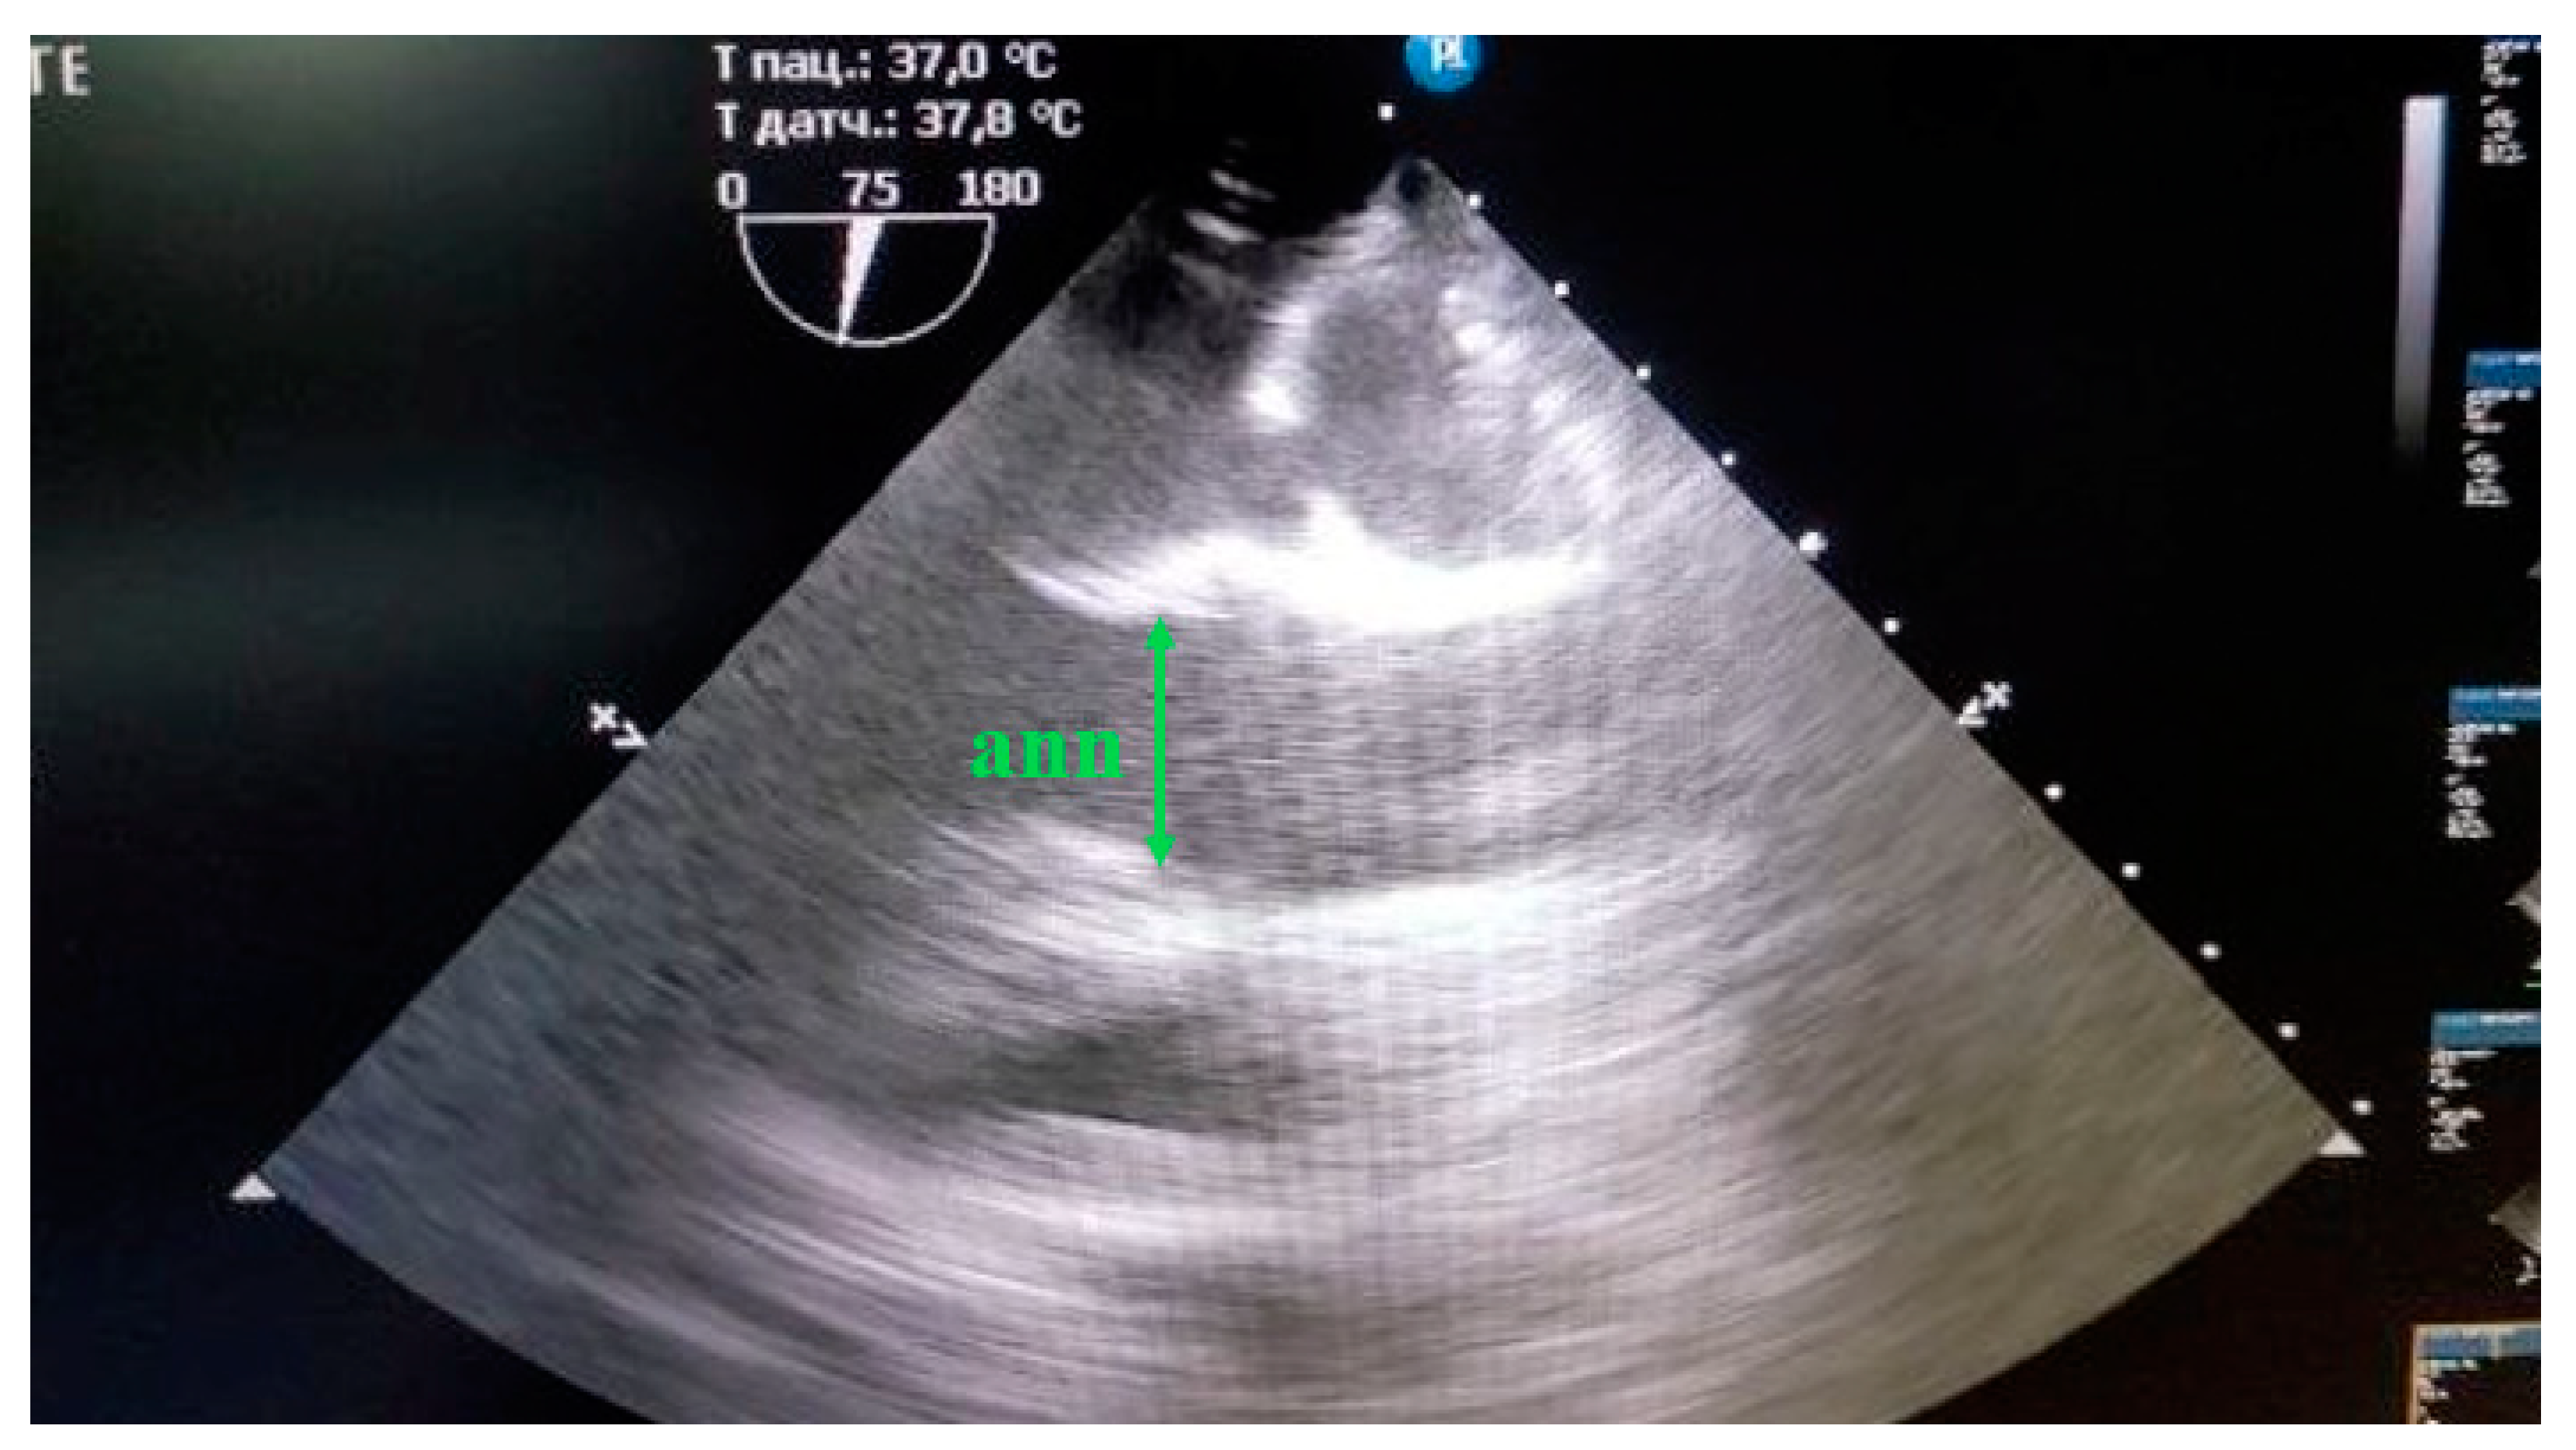

Ultrasound study. Echocardiography was performed according to the methods described for animals [17,18] on a Philips CX-50 ultrasound machine (Revision 3.1.2) with an X7-2t transesophageal sensor. The structures of the aorta were evaluated from the fibrous ring of the aortic valve to the ascending part of the aortic arch. The structures of the aorta located below either were not visualized at all or were poorly distinguished by echocardiography. So, the size of the aorta below the distal arch was estimated by angiography. The fibrous ring of the aorta was measured at the maximum ring size during systole, with the cursor placed from the inner edge to the inner edge at the point of attachment of the flaps (Figure 2).

Figure 2. Measurement of the fibrous aortic ring (ann) in mini pigs from the "inner edge to the inner edge" at the site of flap attachment, in the position with the maximum ring size.